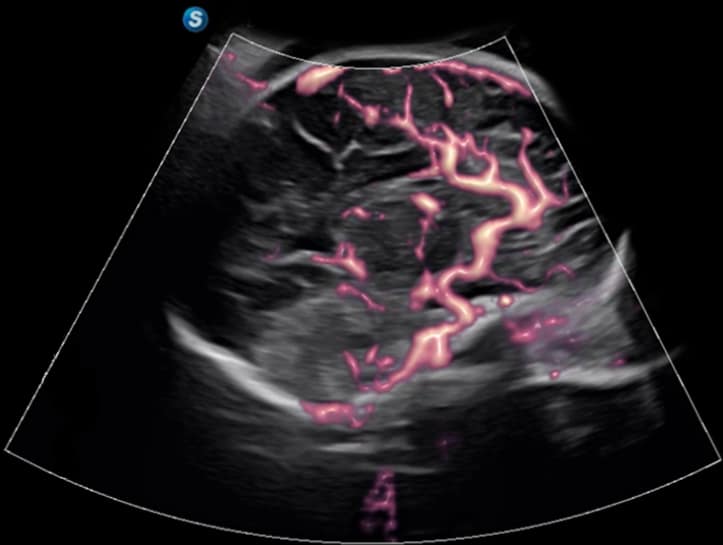

• Micro F: Trennt subtile Blutflusssignale effizient von Gewebebewegungen, um die Mikrozirkulation präzise darzustellen.

• FHR: Erhöht die Empfindlichkeit bei der Beobachtung mikrovaskulärer Strukturen in Organen.